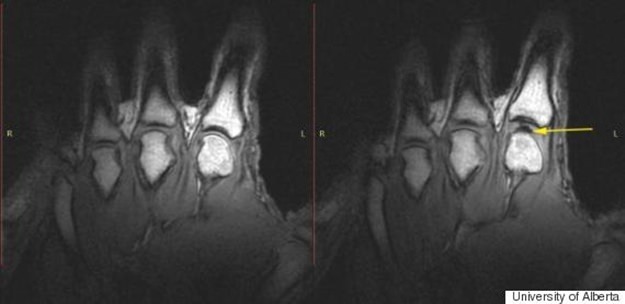

Öncelikle parmaklarımızı kütlettiğimizde neler olduğuna bir bakalım. Sıvıyla dolu olan iki kemiğin birleştiği eklem kapsülündeki boş kısım, parmaklarımızı her kütlettiğimizde genişliyor ve buradaki sıvı kemikler arası boşluğu doldurmak için yetersiz kalıyor. Basıncın düşmesi ve sonrasında oluşan gaz dolu kabarcık, parmaklarımızı kütlettiğimiz sırada o meşhur sesin çıkmasını sağlıyor. Yani bu sesin arkasındaki tek şey bir kabarcık tanesi.

40 denekten alınan verilerle bir analiz yapan Dr. Robert D. Boutin, bu deneklerden 30’unda kütletme alışkanlığının olduğunu, 10’unun ise bunu hayatlarında hiç denemediğini ortaya çıkardı. Bir nevi eklemler için ısınma hareketi görevi üstlenen kütletme, eklemlerdeki hareket genliğinin de artmasını sağlıyor hatta eklem hastalıklarının önüne geçmesi için iyi bir yöntem bile olabileceği belirtiliyor. Zira test esnasında parmak kütleten kişilerde eklem iltihabı ya da şişlik gibi hastalıklara rastlanmadığı belirtildi.